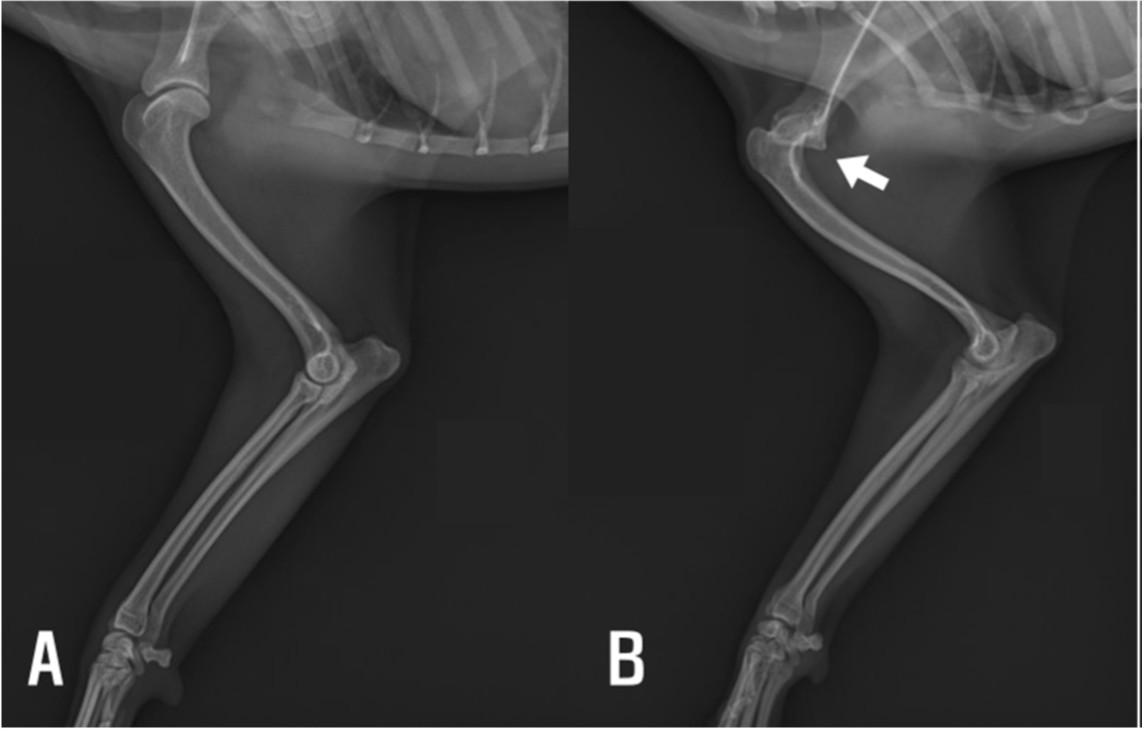

影像检查示左肩胛关节盂及肱骨头发育不良,支持先天性肩关节脱位诊断(图1)。因主人拒绝,未行CT或MRI等进一步影像检查;X线片未见肘部骨性异常,活动受限考虑为关节周围软组织挛缩导致。

图1. (A) 右前肢显示正常盂肱关节对位。 (B) 左前肢显示肱骨头移位,与关节盂变浅相符(箭头)。